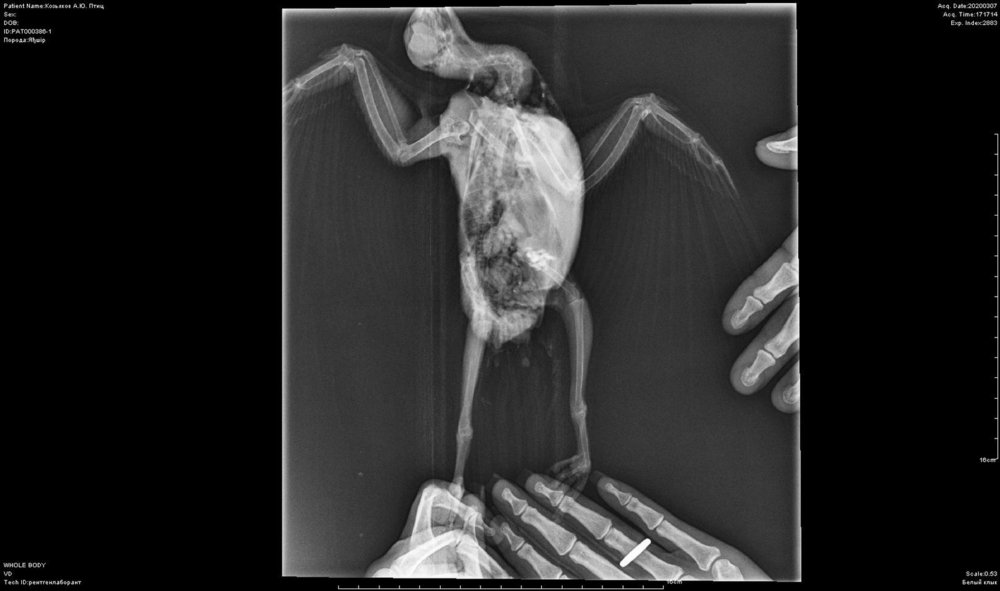

Elena1811 Опубликовано 7 марта, 2020 Автор #113 Опубликовано 7 марта, 2020 Мы старались как могли. Не получается его развернуть полностью из-за левого крыла. Не разворачивается доконца. Боялись сломать

Zosia Опубликовано 7 марта, 2020 #124 Опубликовано 7 марта, 2020 Если есть файлы на флешке- то мне на почту киньте. Т.к. в переснятом виде снимки нечитабельны. zofia68@mail.ru

Elena1811 Опубликовано 11 марта, 2020 Автор #130 Опубликовано 11 марта, 2020 Получила ответ от Зофии. Нужны разъяснения. И некоторые препараты я не могу купить Вот что пишет Зофия: Ну, отличить голубя от голубки я по фото не смогу. Хотя ИМЪО мне видится голубка. И те новообразования в брюшной полости (которые могцт передавливать нервные окончания, идущие к лапкам)- характерны именно для голубок, у меня даже фото есть гранулем, которые у них «рождаются» вместо яиц. Так что ИМХО- итраконазол в дозе 15 мг/кг каждые 12 чсов, нисиатин в дозе 75 000 ед в сутки на 100 гр веса, преднизолон из арсчета 3 мг/кг в сутки. Первый курс- 21 день. Для прикрытия преднизолона- Деринат капли назальные, принимать орально 4 капли в сутки весь курс. Обязательно гепатовте- 0,2-0,3 мл в сутки. По крылу- ваш снимок не дает возможности оценить фатальность нарушений. Но скорее всего- там уже вряд ли что можно сделать (и по-любому это вопрос-не вопрос жизни). ......... У нас беда с преобретением лекарств, рецепты только лишь на аналгин не нужны..